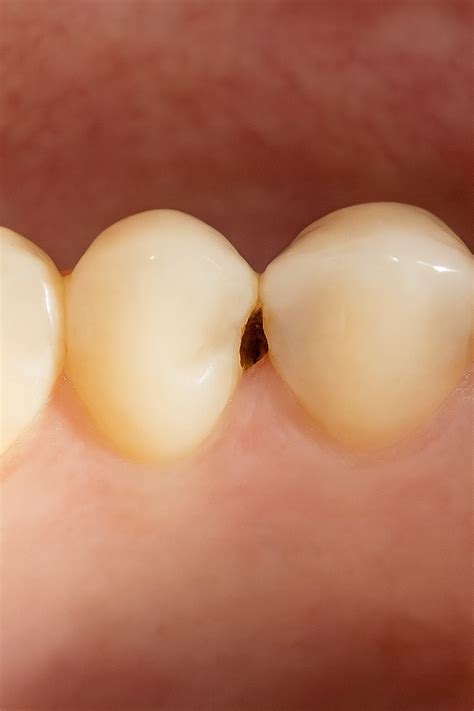

Caries Interproximal

La caries entre los dientes se denomina «caries interproximal«. La carie se crea debido a la placa bacteriana que se acumula a causa de alimentos azucarados y de alto nivel de ácido.

Una carie interproximal es una carie entre los dientes. Se produce cuando la placa se queda en el diente y se endurece, y las encías se recubren de sarro. El ácido de la placa elimina los minerales del esmalte externo. Esta erosión provoca que el esmalte se descaste, la cual se denominaría la primera fase de una caries.

Una forma de detectar la caries interproximal es cuando, al pasar el hilo dental, notamos que se engancha y provoca dolor.

Las caries interproximales son más difíciles de detectar y, al afectar a más de un diente, son especialmente graves.

Por el lugar donde se originan, las caries interproximales pueden ser menos visibles y difíciles de detectar. La zona que está entre los dientes es más inaccesible y durante el cepillado dental será más difícil de limpiar. Por lo tanto es una zona propensa a la acumulación de placa bacteriana y sarro que provoca las caries.

Muchos pacientes se dan cuenta de que tienen una caries interproximal cuando ya sienten síntomas de dolor y sensibilidad dental, momento en que la caries ya ha erosionado parte de la estructura dental.